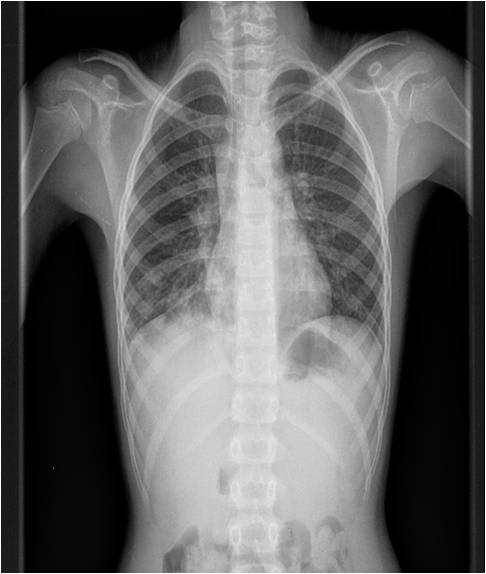

Tras la anamnesis y la exploración clínica, se decide realizar una radiografía de tórax, ¿qué respuesta se adecua más a los hallazgos radiológicos encontrados?